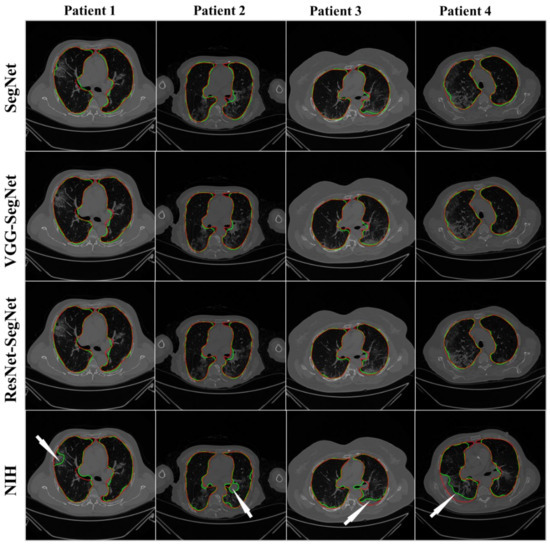

4.2.1. Visualization of Lung Boundary and Regional Lung Error